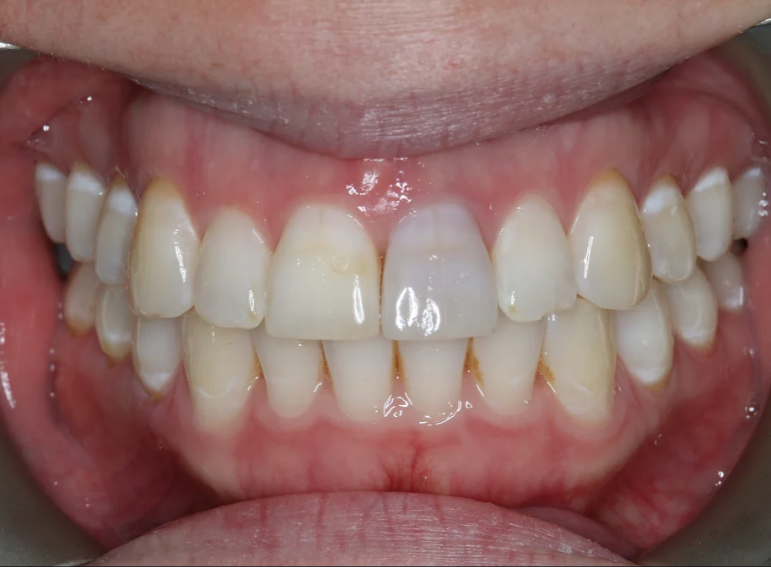

Root canal treatment and combined internal and external whitening.